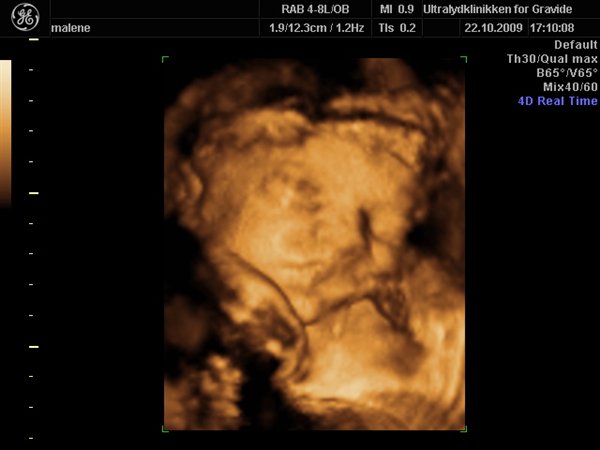

Jeg havde egentlig besluttet fra start af at jeg ville bestemt ikke smide penge efter en 3D scanning, men må indrømme jeg blev fristet

Så vi fik en hurtig tid i eftermiddags, og kom op og vinke lidt til den lille meget stædige prinsesse som vi så fint bekræftet hun er

Hun har allerede nu en masse hår på hovedet, og ligger meget dybt i bækkenet, så det var ikke muligt at få hele hovedet med, da man jo ikke kan scanne igennem knogler.

Hun var lige som hun skulle være, og vejer 1200 g

Vedhæftede fotos (klik for at se i fuld størrelse)